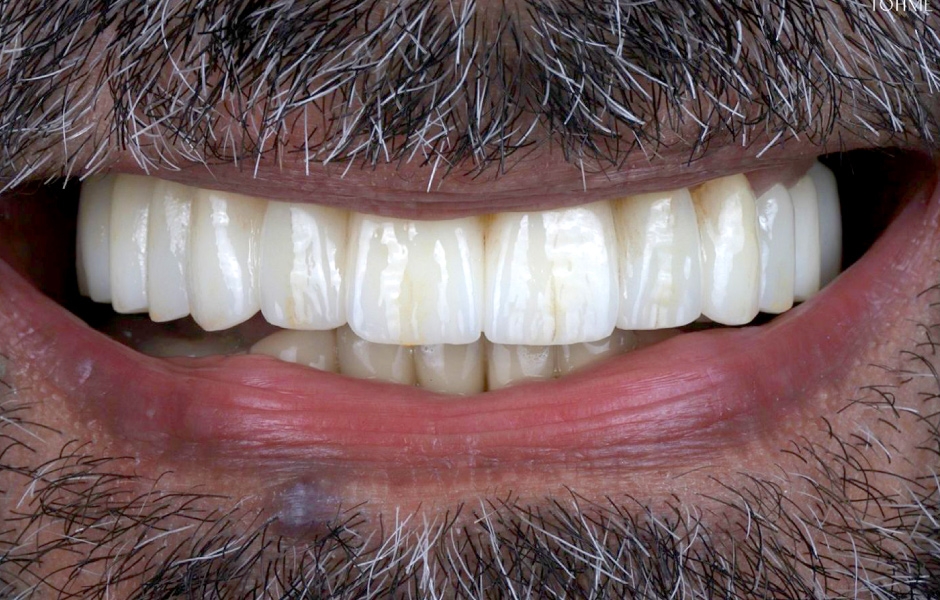

Definitivní náhrada byla nasazena a ověřena z hlediska estetiky, okluze a funkce (obr. 51–55). Panoramatický kontrolní snímek potvrdil, že všechny parametry protetického ošetření odpovídají očekávaným hodnotám (obr. 56).

Při kontrole po 18 měsících po dokončení ošetření bylo provedeno intraorální, extraorální a radiografické vyšetření. Nebyly zjištěny žádné patologické nálezy a výsledné parametry zůstaly stabilní (obr. 57–62).

Obr. 51

Obr. 52

Obr. 53

Obr. 54

Obr. 55